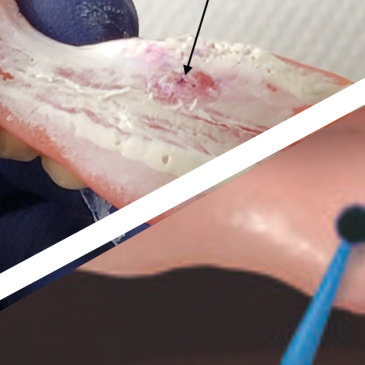

Un patient présente des triangles noirs inesthétiques au niveau antérieur. Grâce à la technique de composites interproximaux avec matrices BioClear BT Matrix, une solution esthétique et conservatrice est mise en œuvre pour fermer les triangles noirs et restaurer l’harmonie du sourire, tout en respectant la santé parodontale.… Lire la suite